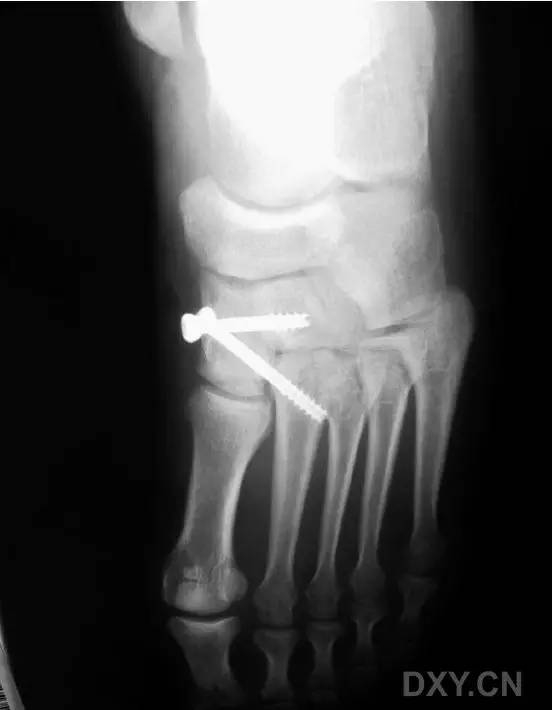

然而这种固定方式存在一大缺陷,那就是,一旦出现螺钉的断裂,将导致螺钉头端取出困难(图 2)。

图 2. 传统 Lisfranc 螺钉置入后,螺钉断裂,位于第 2 跖骨基底的螺钉尖端难以取出